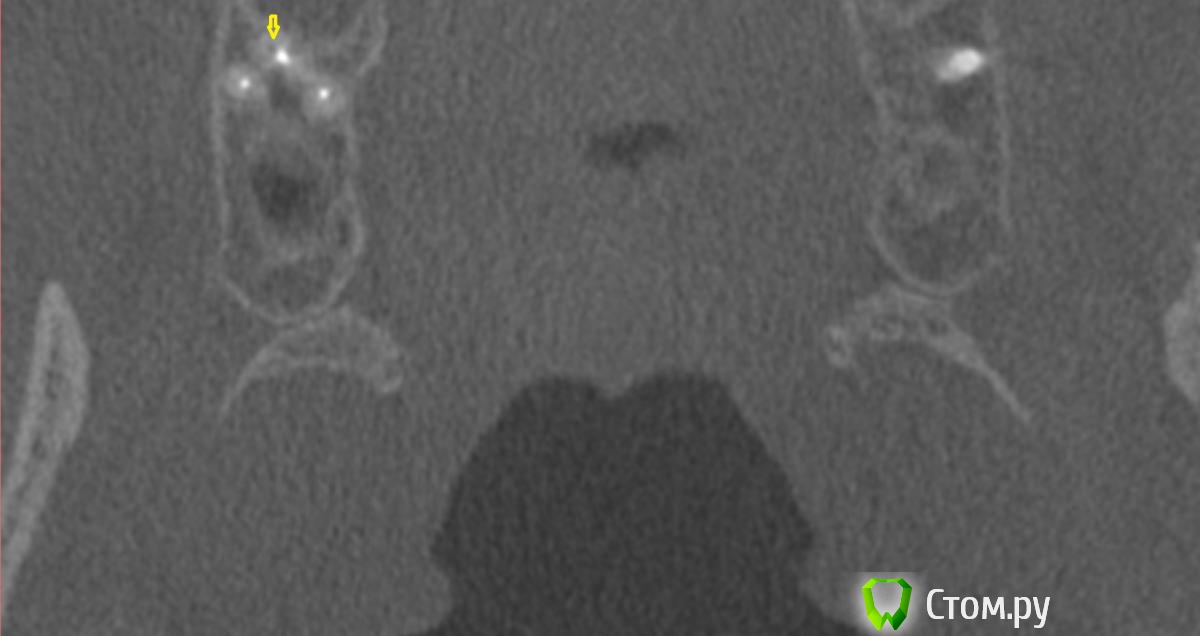

dr-krasnov Опубликовано 10 июня, 2014 Поделиться Опубликовано 10 июня, 2014 Добрый день. На томограмме ретенционная киста слева, одонтогенный синусит справа, замыкательная кортикальная пластина в области корня уже отсутствует. (желтые стрелки) С моей точки зрения необходимо эндоперелечивание причинного зуба. К лору можно сходить за рекомендациями по поводу ретенционной кисты. Обычно с ними ничего не делают, пока они не беспокоят. 1 Ссылка на комментарий

dr-krasnov Опубликовано 10 июня, 2014 Поделиться Опубликовано 10 июня, 2014 (изменено) Тэкс, посмотрел КТ. Претензий к лечению зуба не имею. 4й канал найти не удалось. То был ограниченный артефакт от запломбированного канала. Связи между этим зубом и реакцией слизистой скорее всего нет. Да и синусита нет. Изменения слизистой скорее имеют гиперпластическую природу. Источником исходных реакций послужили уже отсутствующие зубы. Архивные снимки расставили бы все точки над и. Несколько картинок: Небный на осях, можно придраться к незначительному расширению периодонтального пространства апикально, но я бы не стал http://s018.radikal.ru/i515/1406/b8/d712dd4f6158.jpg Дистальный щечный http://s020.radikal.ru/i710/1406/4f/990608ed482a.jpg Мезиальный щечный http://s018.radikal.ru/i518/1406/52/534d8d8534ec.jpg В общем, признаков периодонтита не вижу, рентгенологических показаний для резекции тоже.Я бы порекомендовал динамическое наблюдение. Изменено 10 июня, 2014 пользователем dr-krasnov 1 Ссылка на комментарий